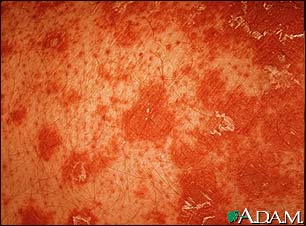

PRP is a chronic skin condition in which orange or salmon-colored scaly patches with thick skin develop on the hands and feet.

The scaly areas may cover much of the body. Small islands of normal skin (called islands of sparing) are seen within the areas of the scaly skin. The scaly areas may be itchy. There may be changes in the nails.